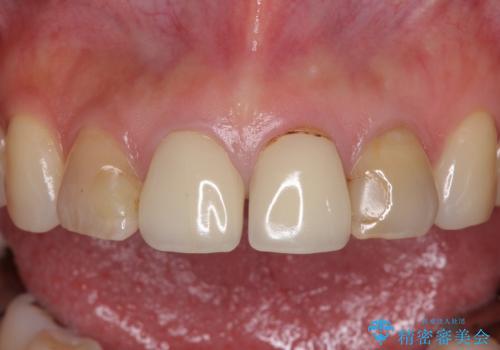

- 前歯のクラウンの変色や歯の変色を気にして来院された患者様です。

グラスファイバーを用いた土台により歯質を強化した上で、オールセラミッククラウンにて補綴することとしました。